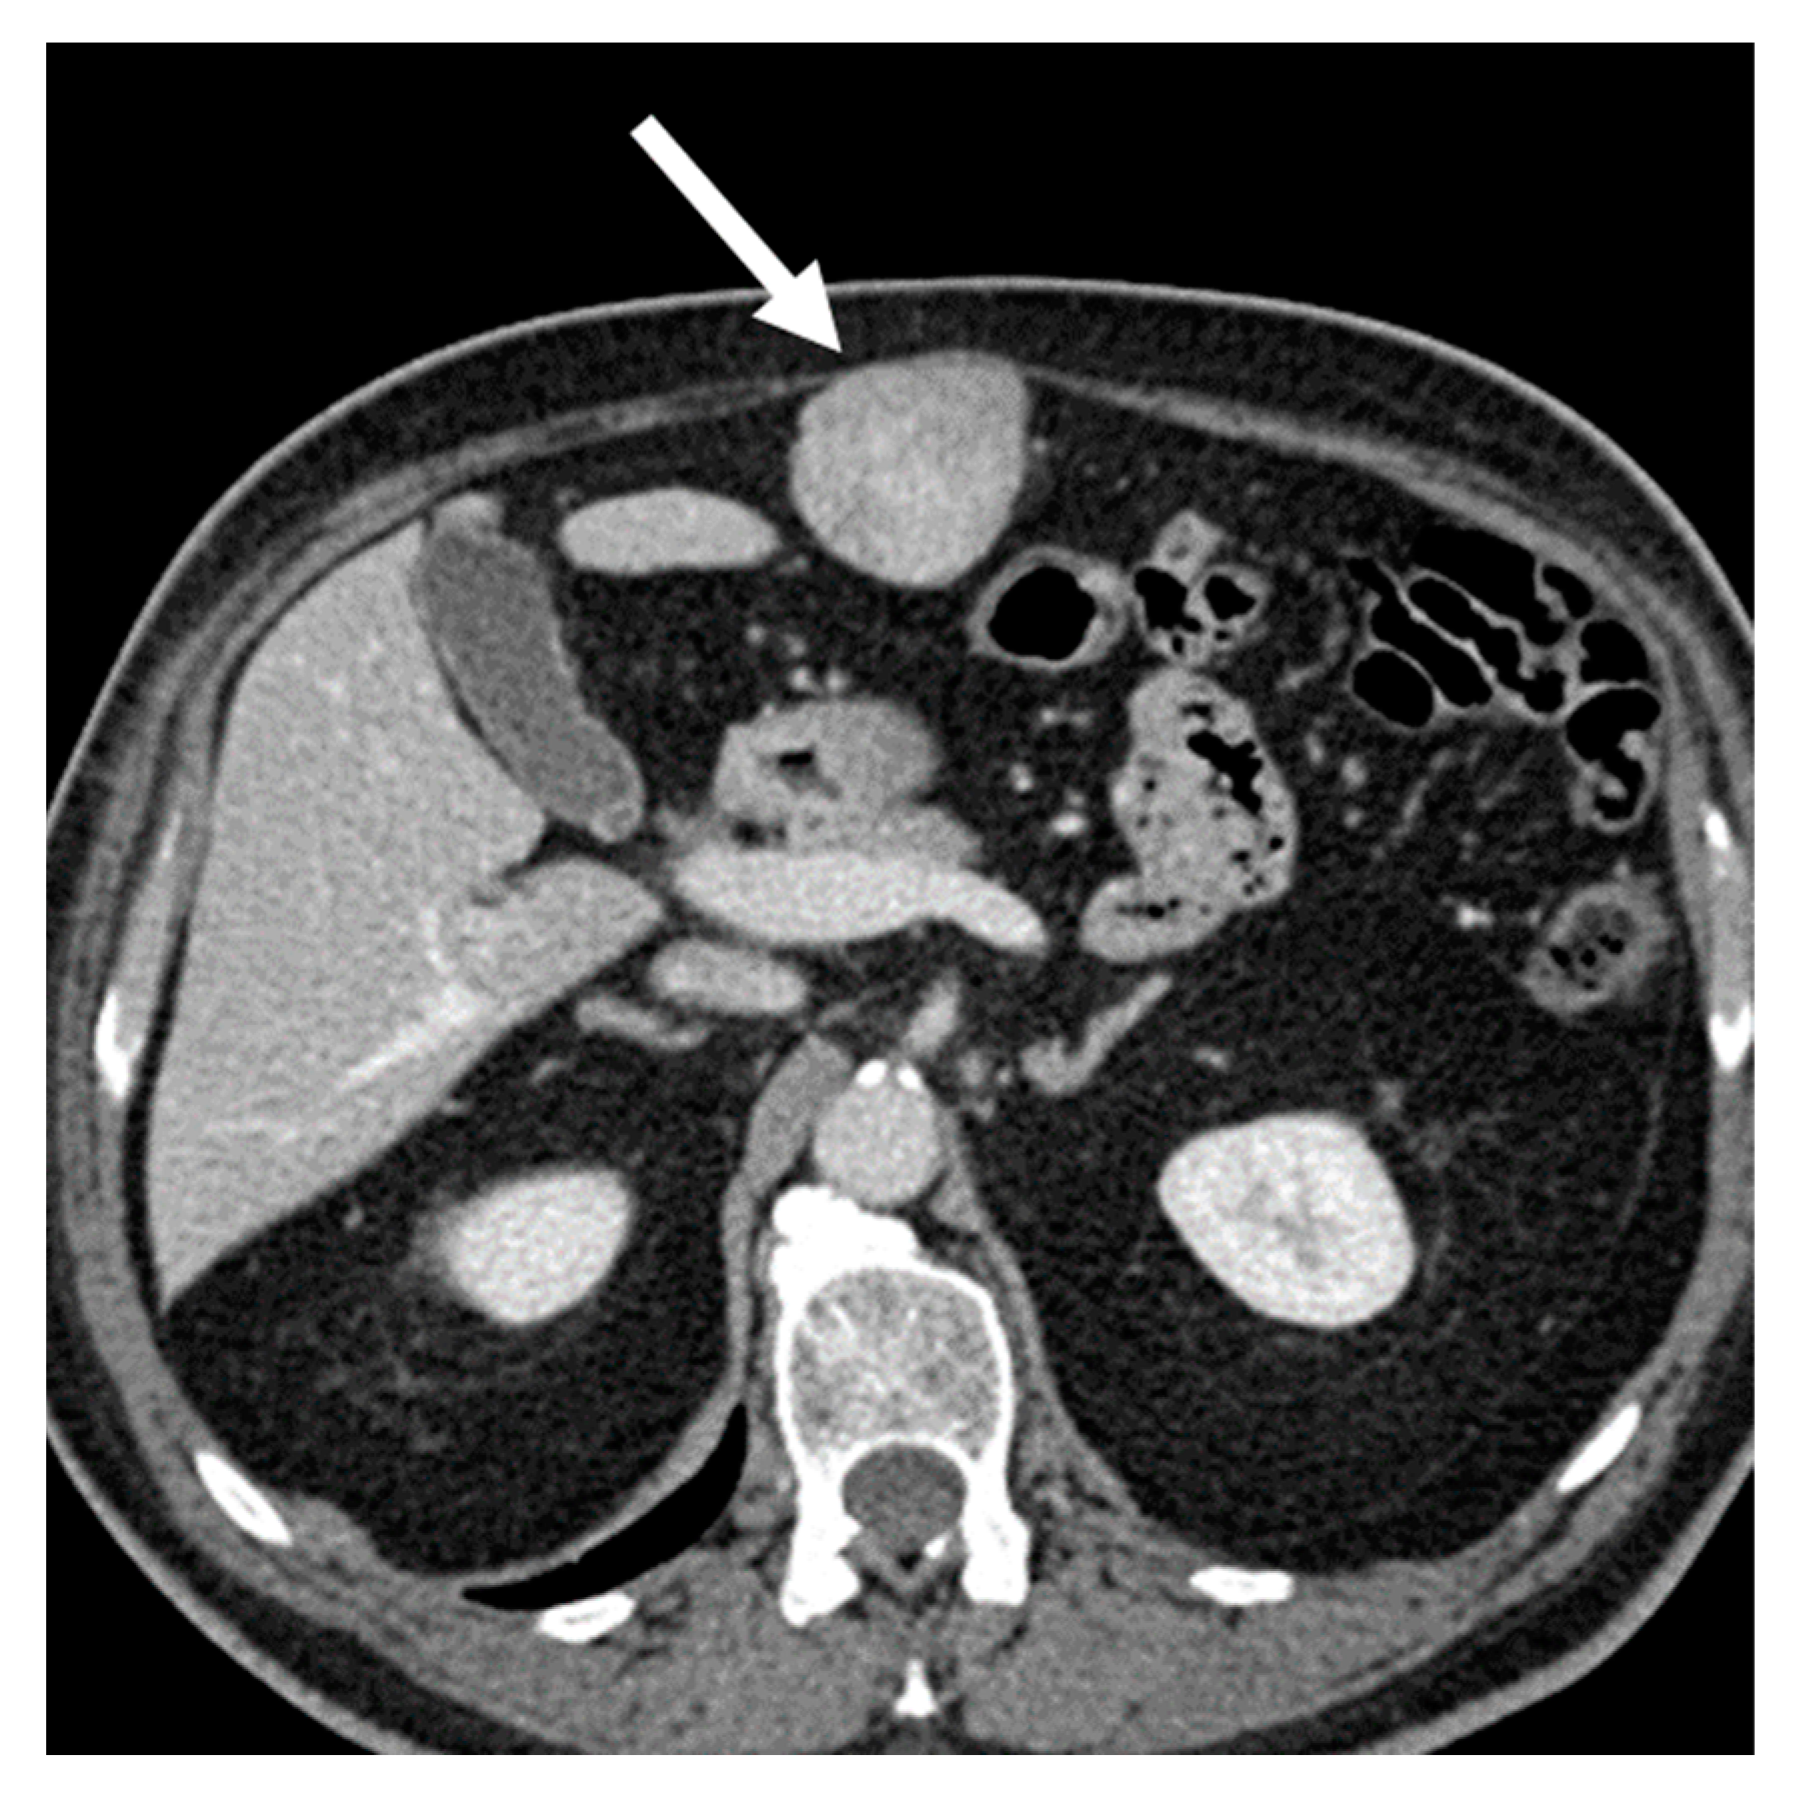

- The beak (claw) sign: when a mass deforms the edge of an adjacent organ into a “beak” shape, it is likely that the mass arises from that organ (e.g., a notch or an infiltration of the renal hilum, suggests a kidney origin of the tumor in the differential diagnosis between LPS and angiomyolipoma (Figure 7) [11,46]).

Figure 7. Renal angiomyolipoma in 62-year-old man. Axial CT images on the pre-contrast (A), arterial (B), and venous (C) phases and coronal venous (D) phase show a 4.5 cm heterogenous adipose lesion deforming the edge of the right kidney with a “beak” shape appearance (claw sign, arrows). - The embedded organ sign: when there is intimate contact between the mass and the organ of origin, a desmoplastic reaction and sometimes ulcerations are observed (positive sign). On the contrary, a moldable, compressed organ will be deformed into a crescent shape (negative sign). The latter is useful for example in the differential diagnosis between RP leiomyosarcoma and primitive inferior cava leiomyosarcoma [36,46].

- The sandwich (or hamburger) sign (Figure 8): presence of a mesenteric nodal mass that envelops mesenteric vessels on both sides, without grossly infiltrating them. This is a classic sign of mesenteric lymphoma (typically non-Hodgkin) or posttransplant lymphoproliferative disorder in transplanted patients.

Figure 8. Non-Hodgkin lymphoma in 62-year-old man. Axial CT images on the pre-contrast (A) and venous (B) phases show multiple confluent retroperitoneal and mesenteric nodal masses on both sides of the upper abdominal vessels (sandwich sign).